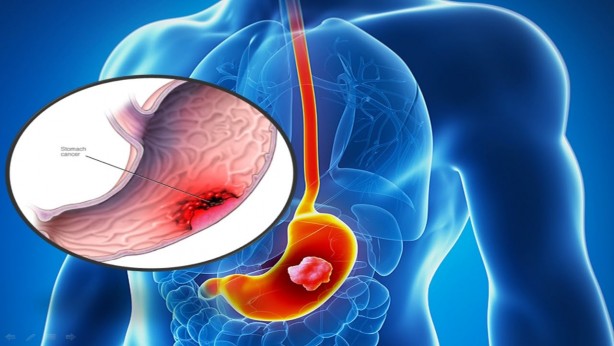

Bu 5 belirtiye dikkat! Mide kanseri olabilirsiniz

Mide kanserine yakalananlar genelde doktora hazımsızlık şikâyetiyle gidiyor. Hastalığın başlangıcında sinsi ilerlediğini söyleyen uzmanlar, mide kanseri belirtileri hakkında bilgi verdi.

Mide kanserine yakalananlar genelde doktora hazımsızlık şikâyetiyle gidiyor. Hastalığın başlangıcında sinsi ilerlediğini söyleyen uzmanlar, mide kanseri belirtileri hakkında bilgi verdi.

Mide kanseri dünyada kansere bağlı ölümlerde dördüncü sırada yer alıyor. Mide kanseri belirtilerinin başında ise hazımsızlık geliyor.